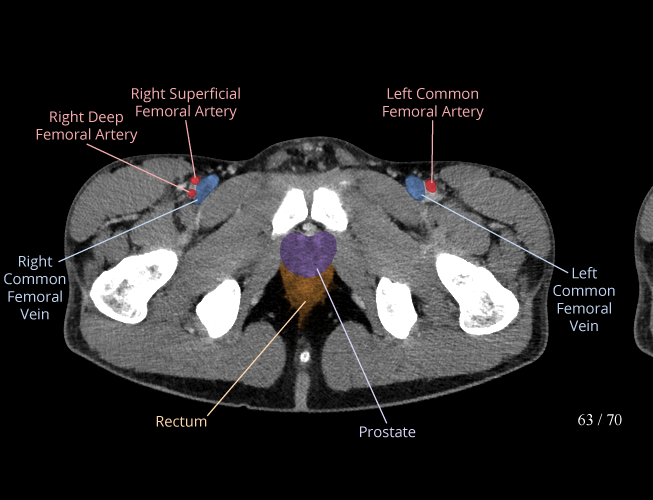

Pelvis

Covers pelvic MRI anatomy.